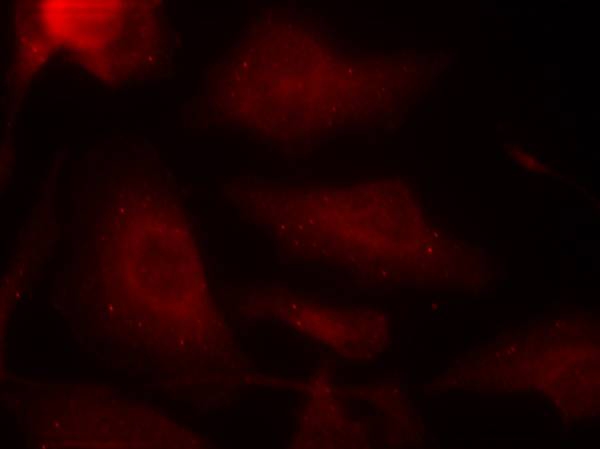

Immunofluorescence staining of methanol-fixed Hela cells using Tau(Phospho-Ser404) Antibody #11112.

Immunofluorescence: 1:100~1:200